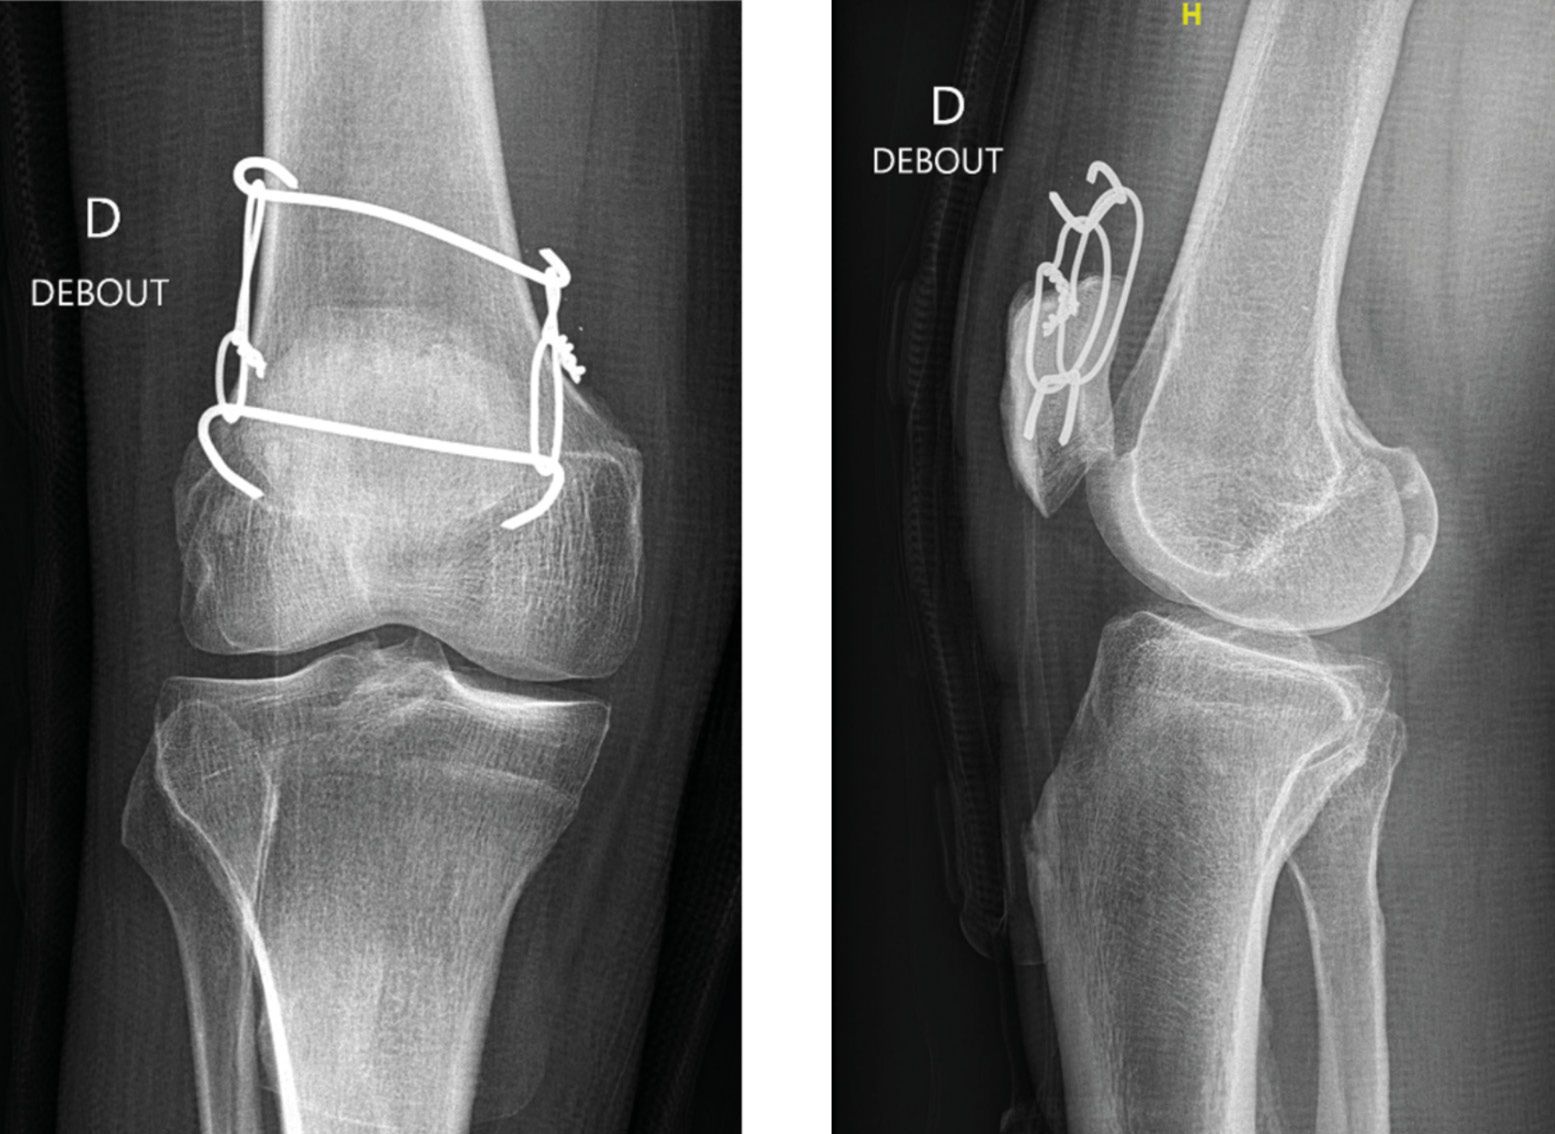

Two 2 mm pins are placed crosswise, one through the patella 2 cm beneath the proximal end, the other through the proximal stump of quadriceps tendon about 2 cm from the tear. The two pins are cut and their ends bent over. Two 2 mm metal wires are then passed in a loop through the ends of the pins. The knee is placed in extension and the retracted stump of quadriceps tendon is gradually moved down towards the proximal end of patella by pulling on the two metal wires (Figure 9).

Once the two stumps of the tendon are touching, the pre-prepared Fiberwire® or Mersuture® sutures from the proximal end of patella are passed through the proximal tendon stump and knotted together (Fig. 10). The procedure is completed with edge-to-edge repair of the tendon using continuous sutures and Polysorb® no. 2 (Covidien®). Stability is then tested by gradually flexing the knee. The final stage is closure of the subcutaneous and skin layers.